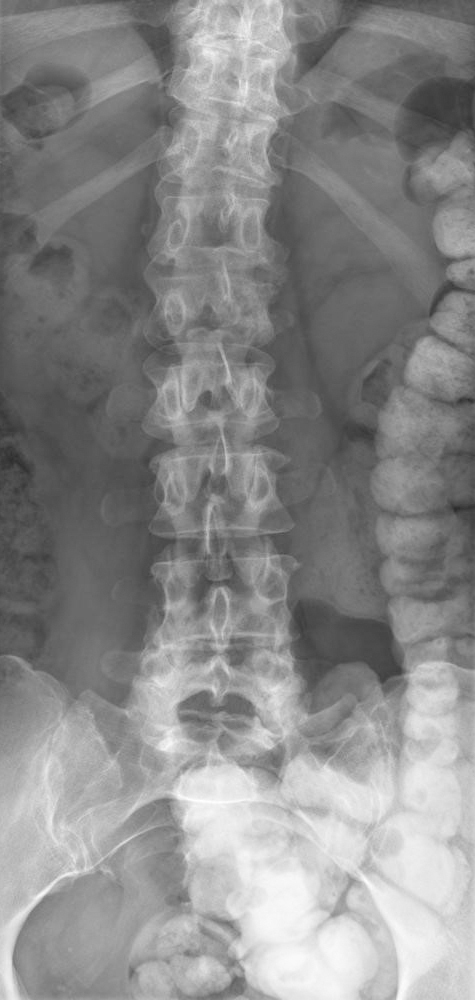

Son médecin traitant lui a prescrit de faibles doses de morphine, ce qui la soulage, et a fait réaliser l’élément suivant.

Question 11 - Concernant le tableau de la patiente (une ou plusieurs réponses exactes) :

Il s’agit d’un effet indésirable connu des inhibiteurs de l’aromatase, mais la perte du pédicule latéral gauche de L2 (vertèbre borgne) est en faveur d’une récidive.

L’aspect de vertèbre borgne est hautement évocateur d’une récidive (envahissement du pédicule latéral).

L’aspect de vertèbre borgne est fortement évocateur d’une récidive tumorale.